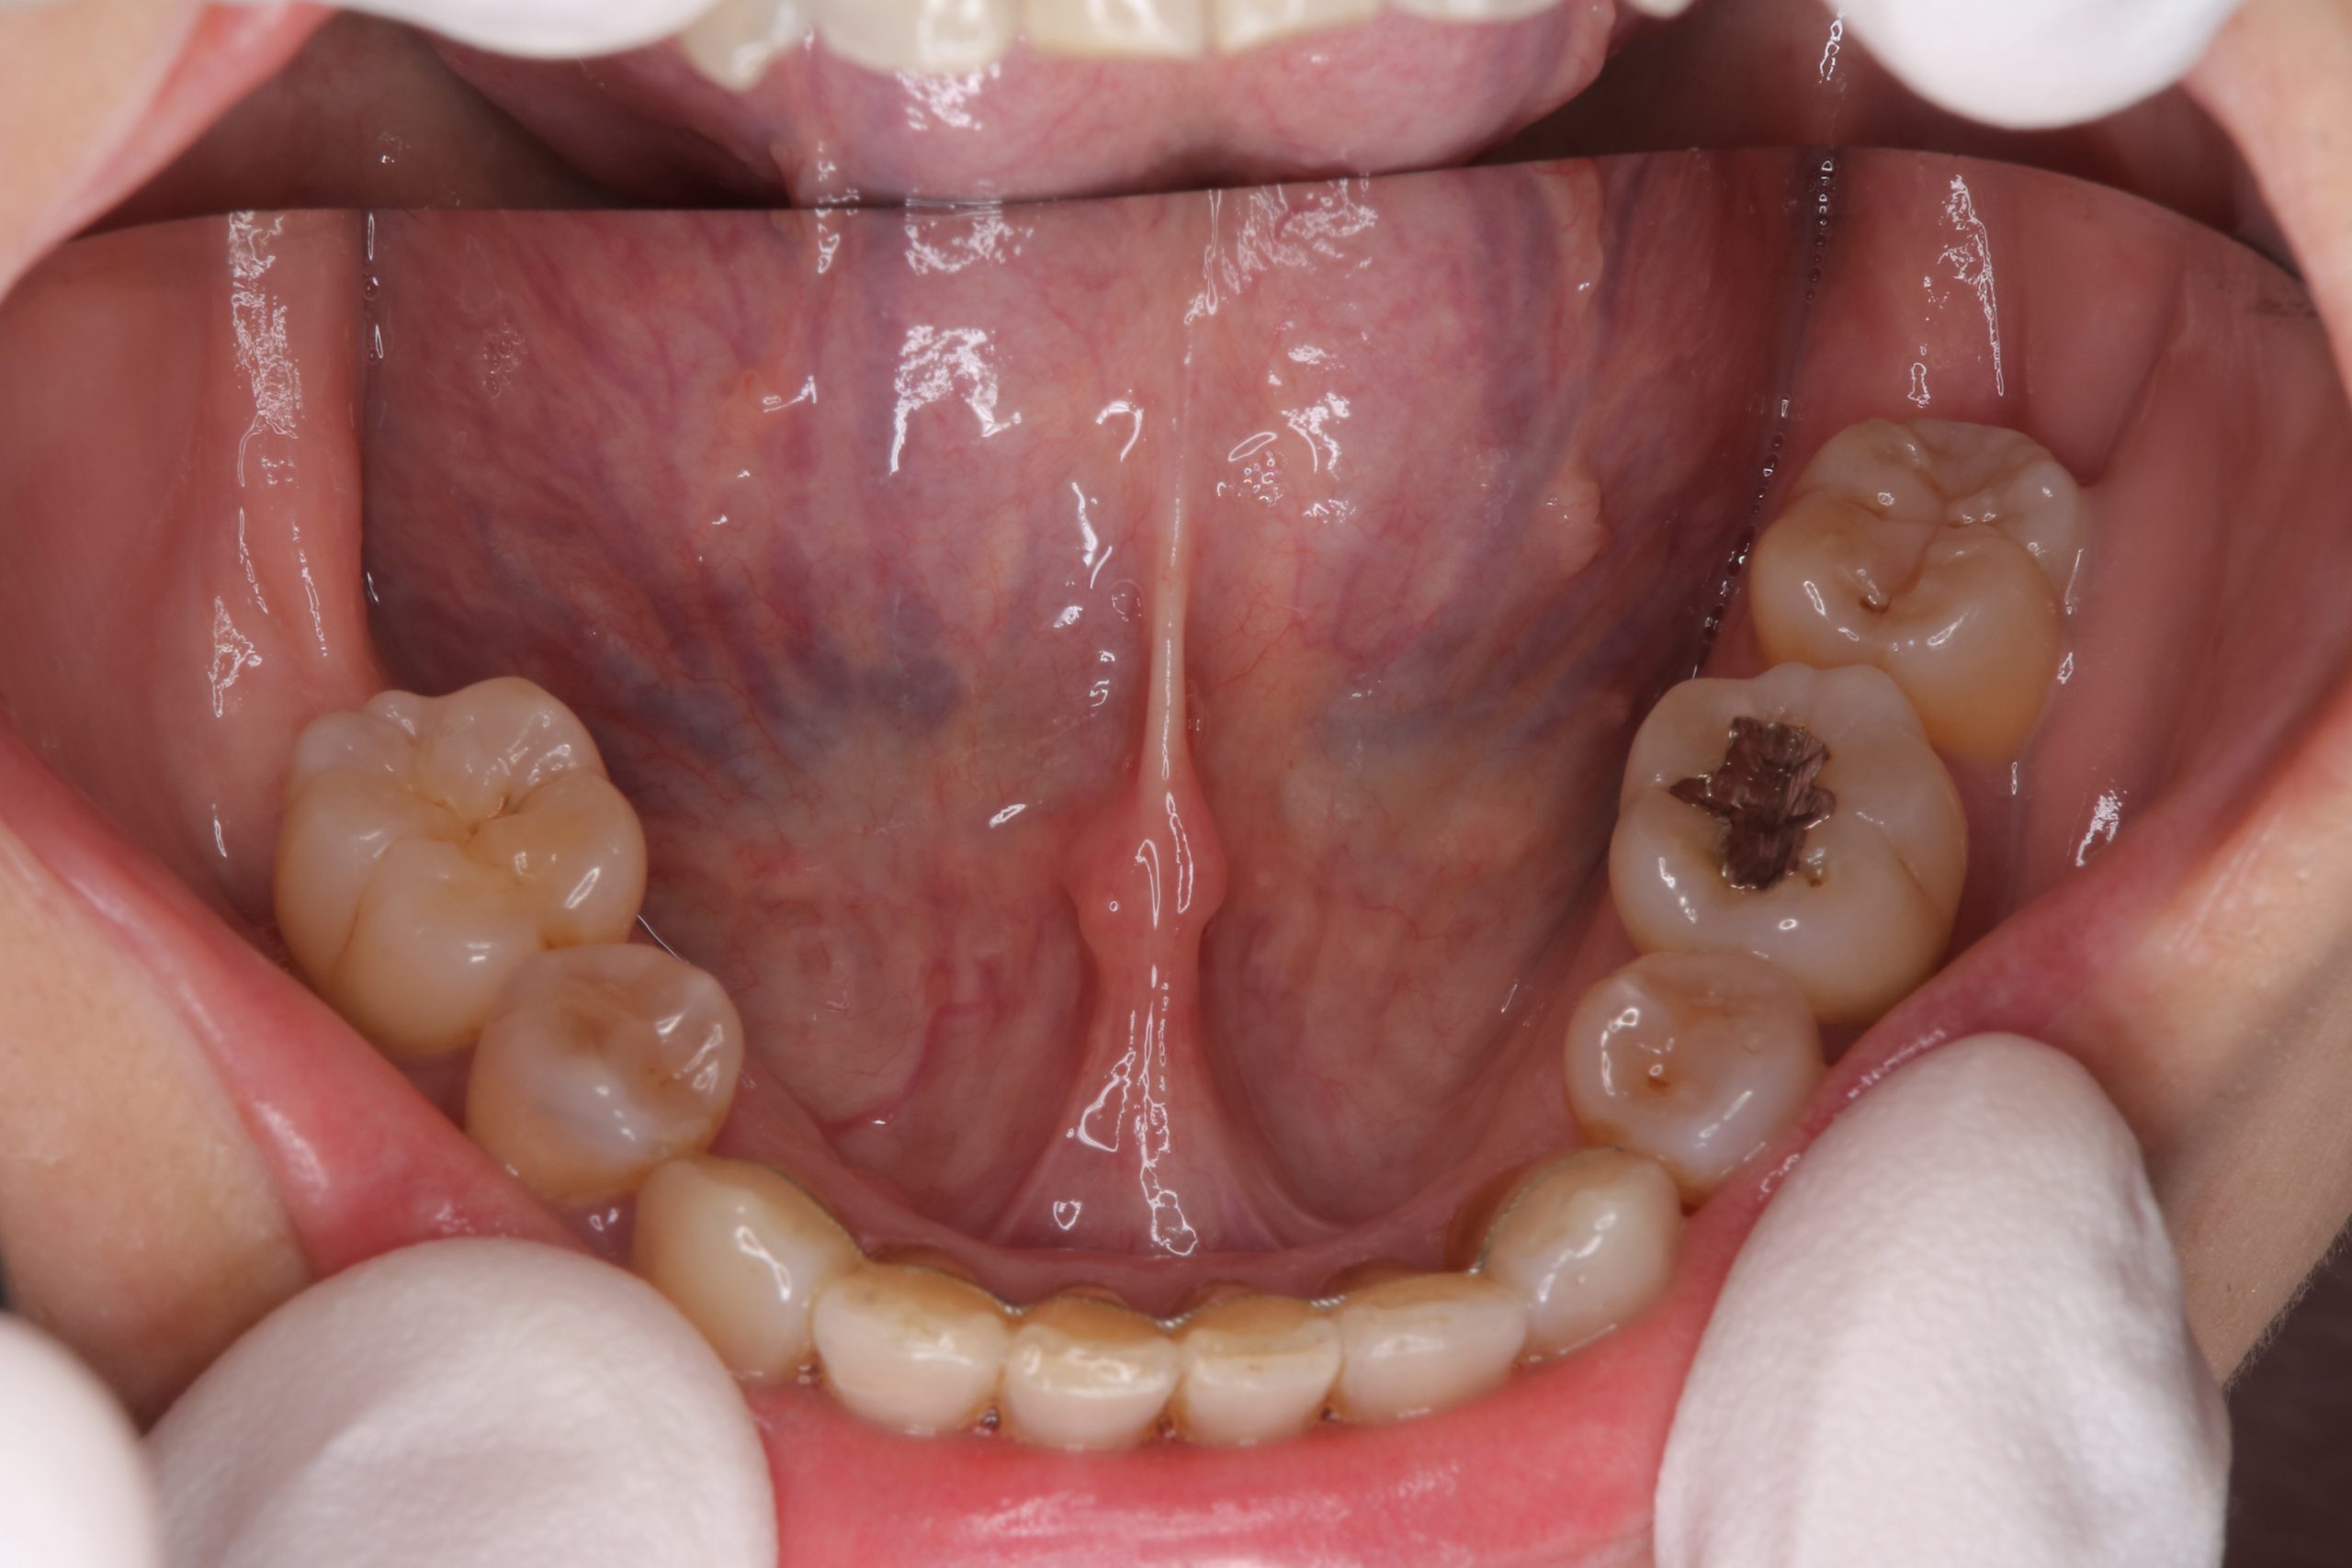

歯周治療症例8

本症例は40代前半の女性で、全顎的な歯周治療を希望され他院より紹介にて来院。

フルマウスエックス線写真(14枚法)と歯周組織精密検査の結果、全顎的に中等度から重度の歯周炎が認められ、左上第二大臼歯(27)は保存不可能(抜歯)であった。また、右上臼歯部(17-14)および右下臼歯部(46-44)にはエムドゲインを応用した再生療法を行い、その他についても全顎的歯周外科手術を行った。

また、著しい歯列不正が口腔清掃状況に悪影響を及ぼしているため、全顎的な歯列矯正を行った。

術後写真は、術後3年の状態であるが歯周組織の状態は安定している。